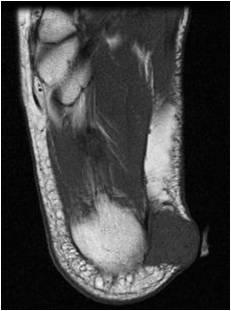

Fig. 1 & 2: MRI Sagittal (Fig. 1) and Coronal (Fig. 2) T1 images of the right foot demonstrating a well-circumscribed soft tissue mass with mildly increased signal compared with muscle, located along the medial aspect of the calcaneous bone. No marrow abnormalities or surrounding soft tissue edema is noted.